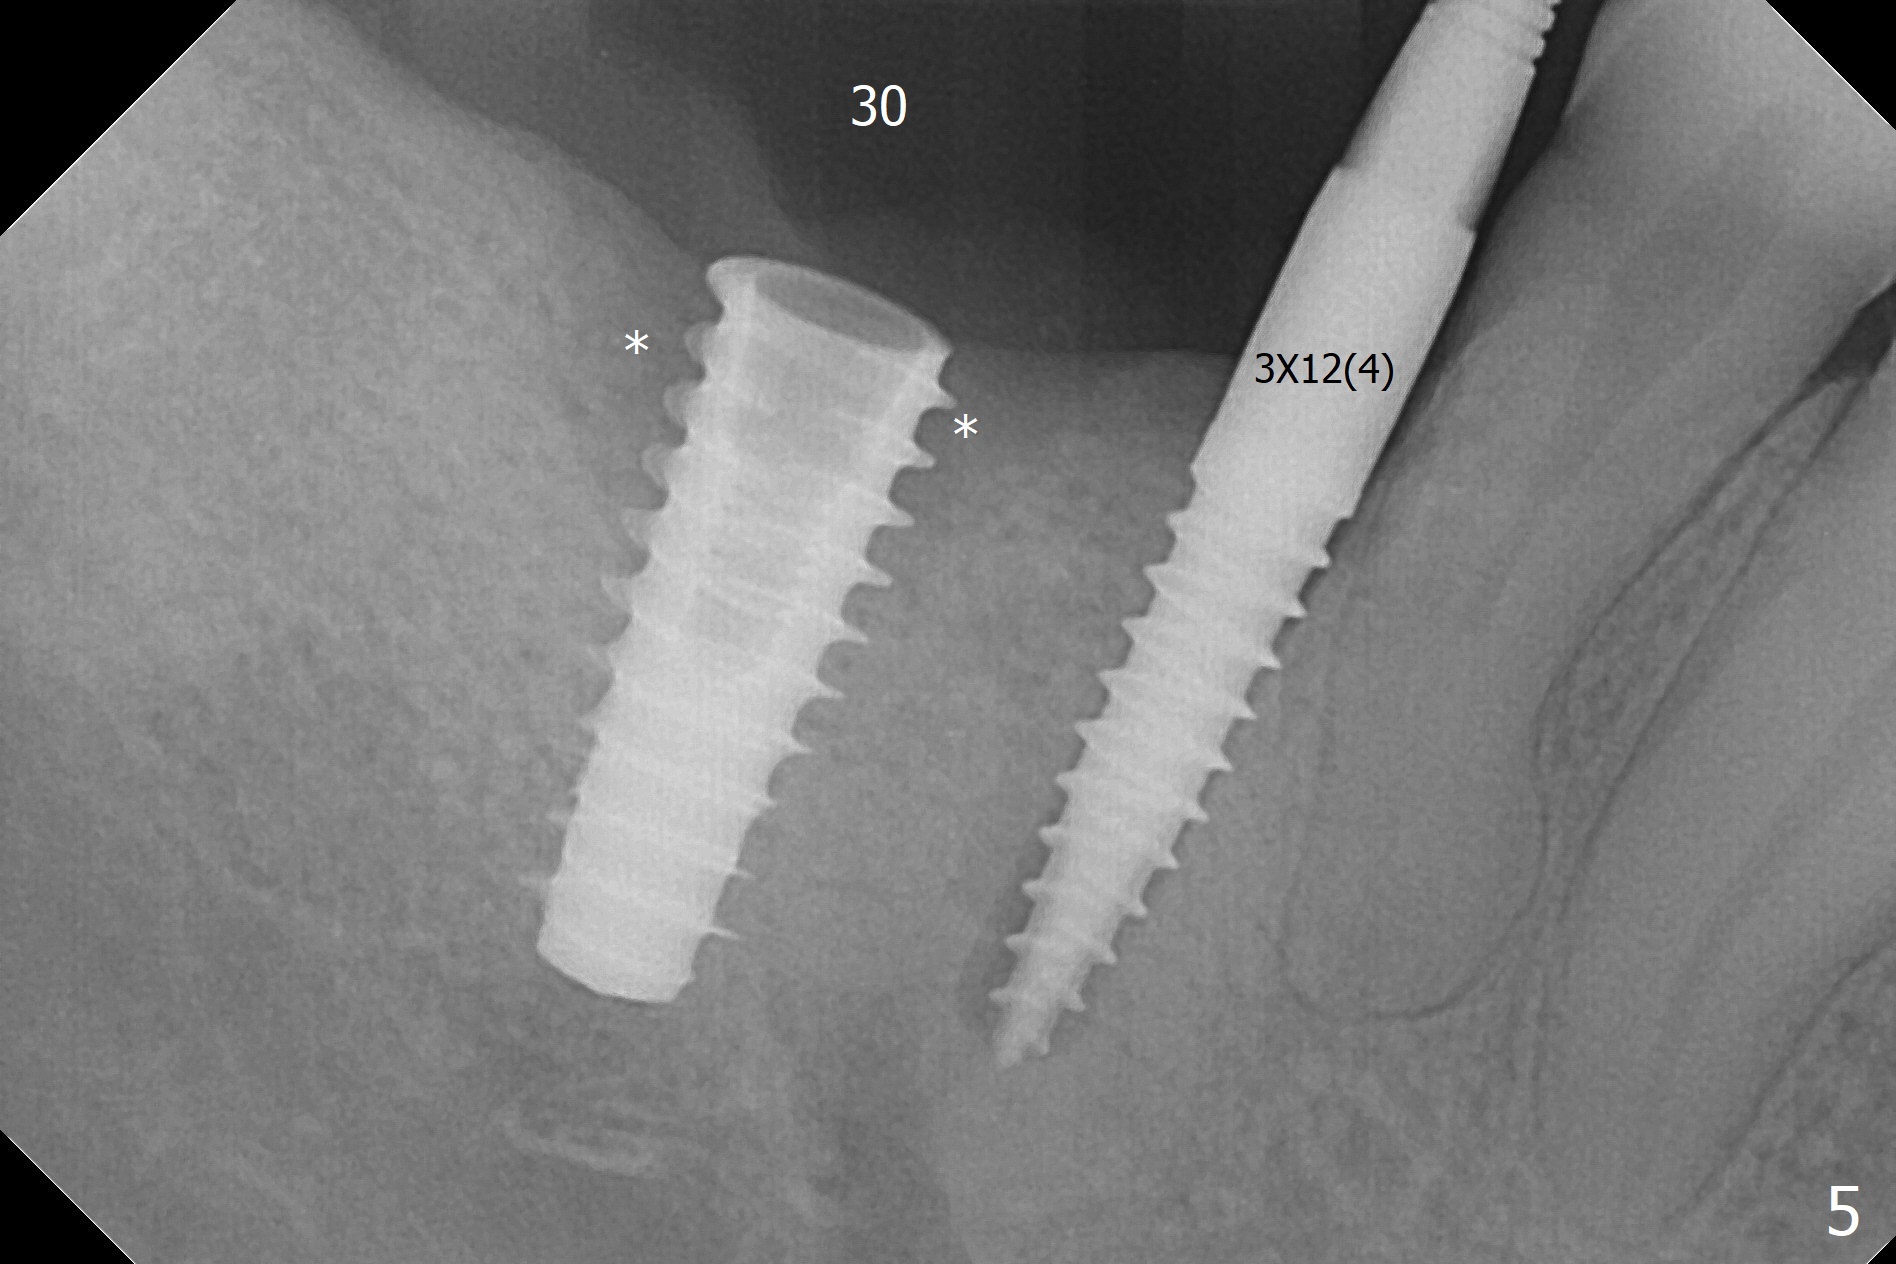

The buccal gingiva is recessive at #29 and 30 (Fig.1). Incision reveals buccal implant thread exposure with circum-ferential granulation tissue (Fig.2 *). Immediate post implant removal at #29, osteotomy is initiated lingual (Fig.3 (intraop CT, coronal section) ). A smaller and shorter implant (3x12 mm vs. 3.5x13 mm) is placed away from buccal (Fig.4 B, 5).

The implant at #30 was also buccally placed (Fig.6,7) and should be corrected in the same manner (Fig.7 green). Due to the bone being harder in the molar region, a smaller and shorter implant (4x11 mm vs. 5x13 mm) shifts slightly buccally while being placed (Fig.8,9). Since primary stability is lower (<20 Ncm vs. 35 Ncm associated with the implant #29), an abutment is not placed, which may be favorable to healing, but it is difficult to achieve primary closure. After bone graft (Fig.9 *) and 2 layers of PRF, Cytoplast is placed. Cytoplast appears to be exposed buccally (Fig.10 <) and occlusally (Fig.11 ^) asymptomatic 9 days postop. Exposure of Cytoplast is more distinct without sign of infection 15 days postop (Fig.12). The patient returns with chief complaint of "foul smell" 7 weeks postop (coronavirus lockdown). Although the Cytoplast exposes more (Fig.13 (* exposed; @ unexposed)), the underlying gingiva remains healthy (Fig.14). While the bone height decreases at #29, the bone density at #30 increases 4.5 months postop (Fig.15). The gingiva heals. The implant at #30 is uncovered 6 months postop. The lingual plate has to be removed for the uncover, while the coronal end of the buccal one is missing. No bone graft is added. When the 4.5x4 mm healing abutment is removed 6.5 months postop, the buccal plate looks concave at #30 (Fig.16' *). The buccal plate looks thin at #29 with a cotton roll placed buccally (Fig.16 R). The lingual plate at #29 is coronal to the buccal one (Fig.17). The buccal gingiva at #29 is quite long (Fig.18). The coronal buccal plate appears to be missing (Fig.19 >), which will be watched. A 4.5x7.5(4) mm cemented abutment is torqued (Fig.20).